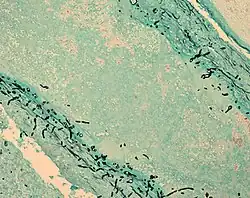

| Fungus (black) in brain tissue | |